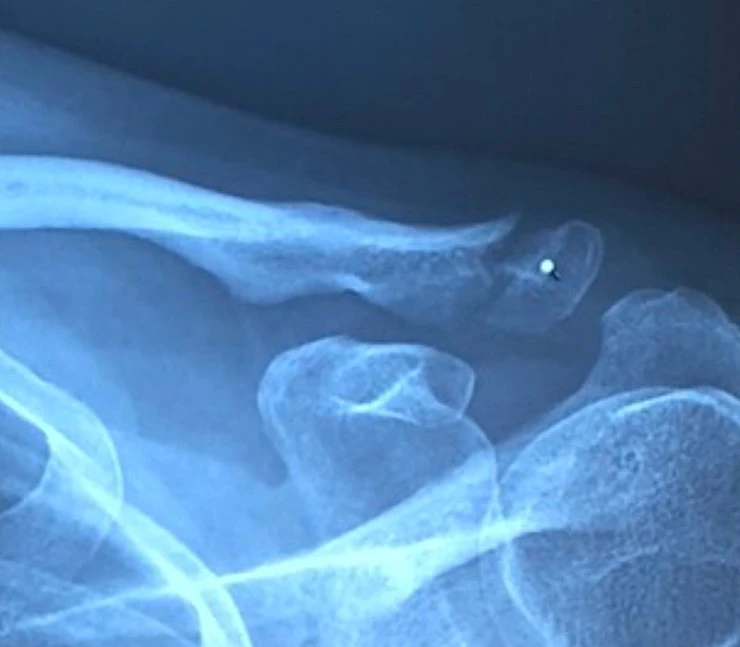

각각 7주차와 5주차의 엑스레이 영상 자료

촉진 중에 환부를 세게 눌러도 보셨는데 전혀 아프지 않았다. 엑스레이 영상에서는 아직 골갭이 보이지만 이건 차차 채워진단다. 완전히 하얗게 다 채워지는데 약 6개월 정도가 걸릴거라고 했다. 집에 와서 사진을 다시 확대해서 보니 희미하게나마 뼈모양대로 이어진 가골이 보인다.